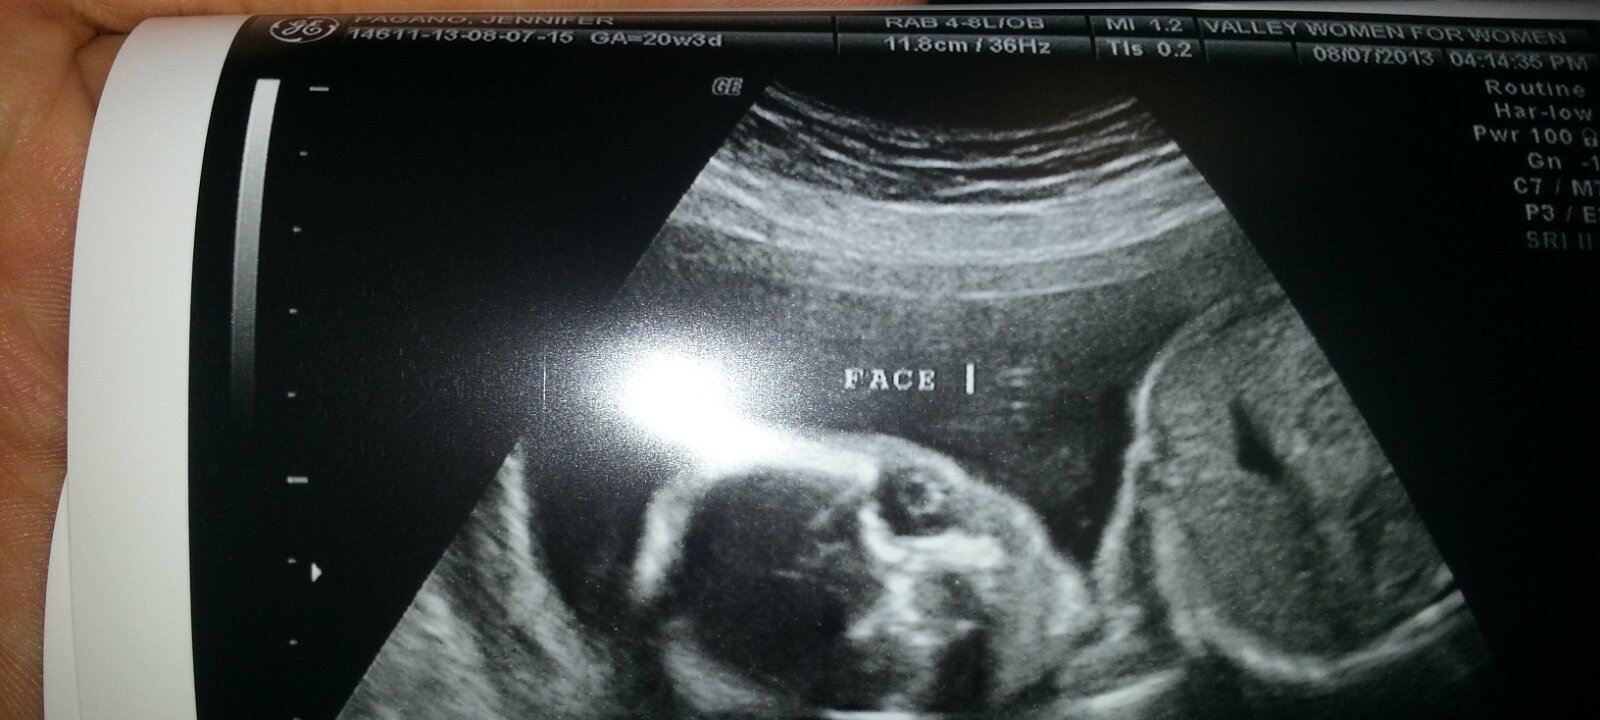

Our Baby

August 7th